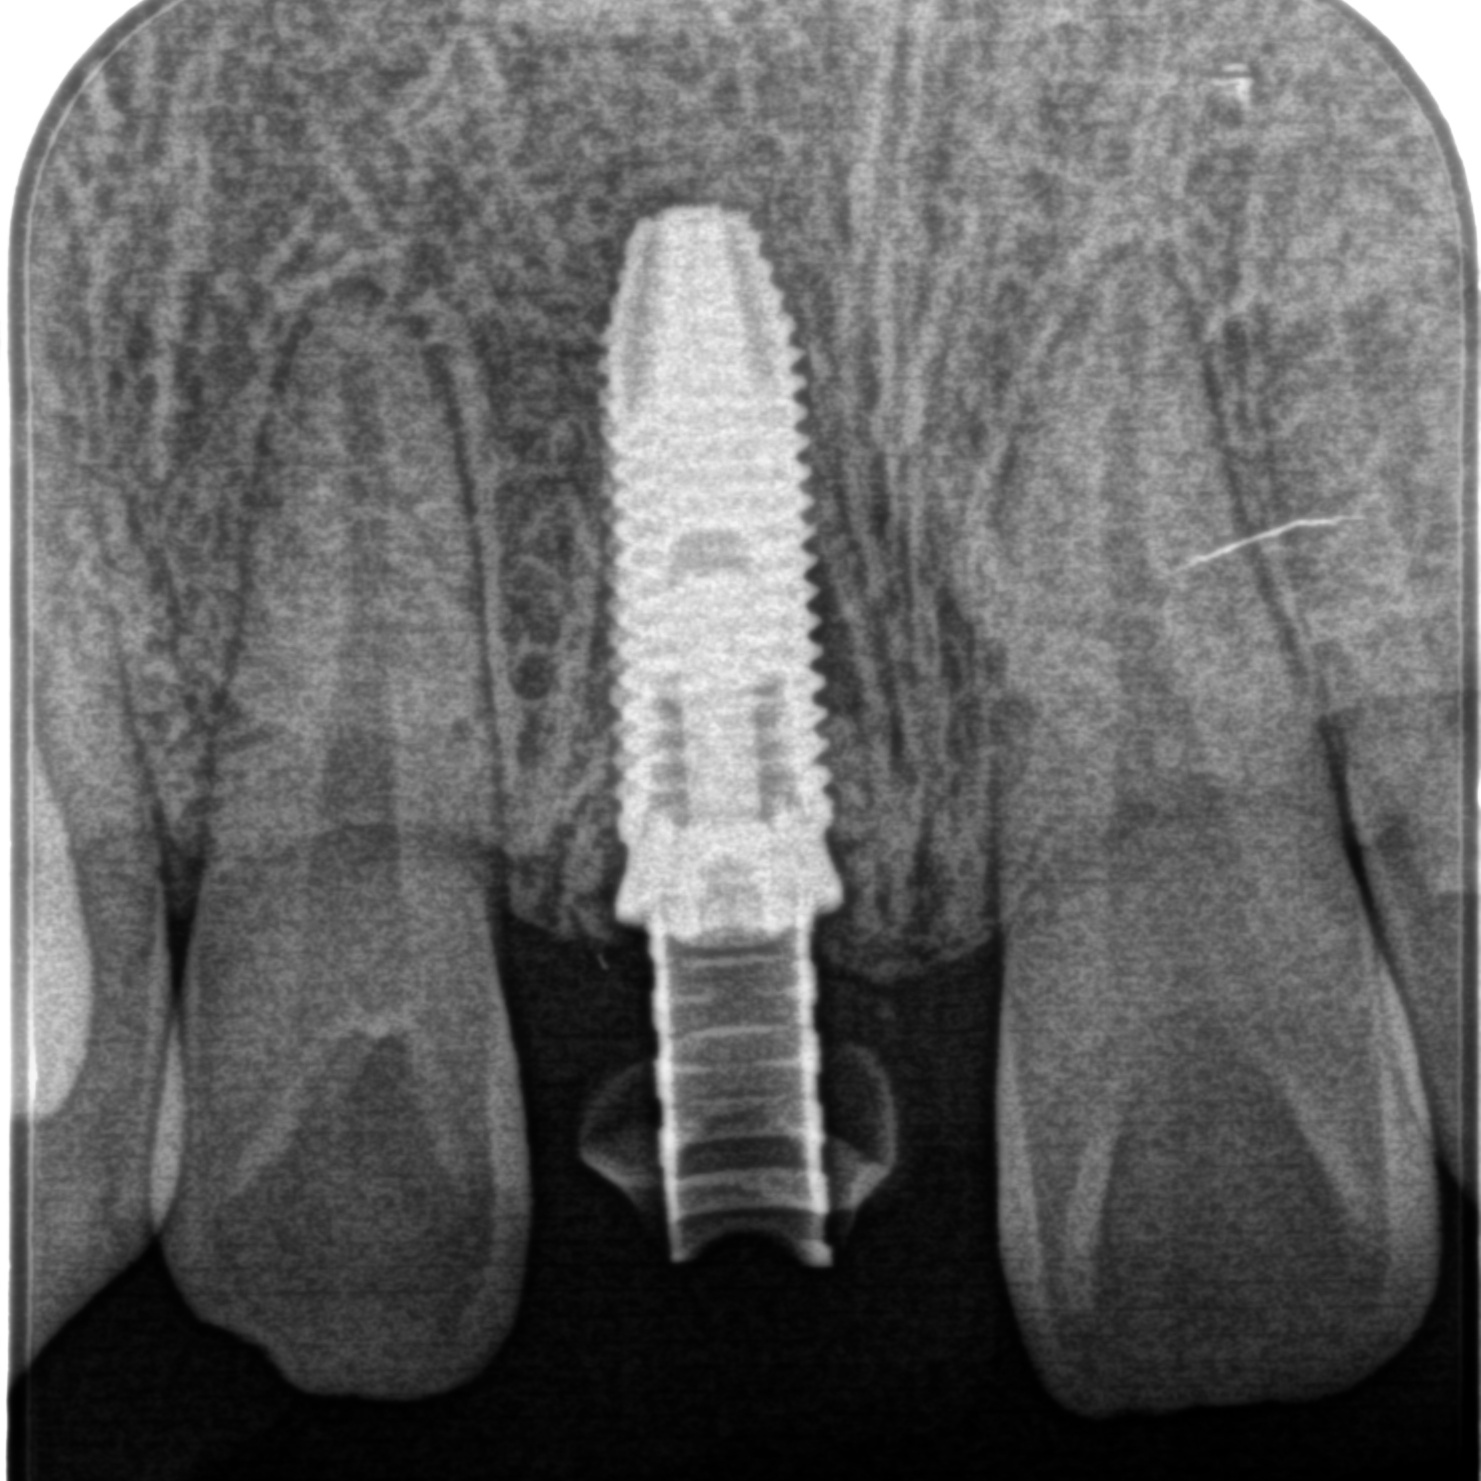

初診時

手術後

・抜歯

・インプラント埋入 1本

※前歯のため、抜歯とインプラント手術を行ったその日のうちに仮歯のセットまで行いました。 - 4